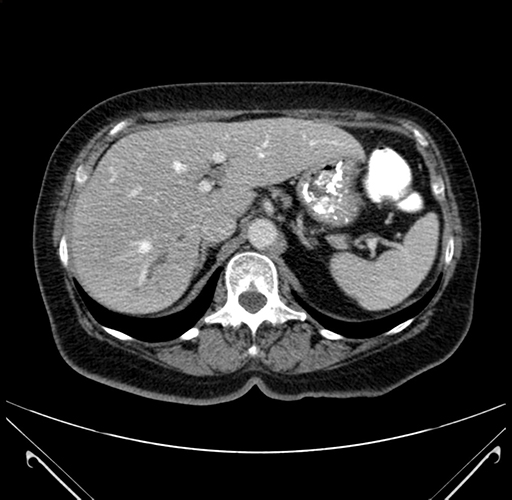

Pre-Chemo: Axial Venous

Imaging analysis

Based on your CT findings, which issue(s) would give reason for "planned slowing down moment(s)" in this case?

Considering a standard right hepatectomy procedure, what step(s) of the operation would you do differently in this case?